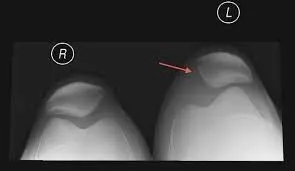

小美述說自己兩腳的膝蓋痛已經有一年了,一開始休息一下都會比較好,隨著時間過去,膝蓋疼痛的情形愈來愈頻繁,從跳躍會痛到走路會痛,甚至最近連久坐的時候,兩小腿都會有抽筋的感覺,連蹲下去都顯得很困難。她拿著X光片跟我說「醫生說是髕骨外翻」接著她又問「為什麼會有髕骨外翻」「那它會回正嗎」